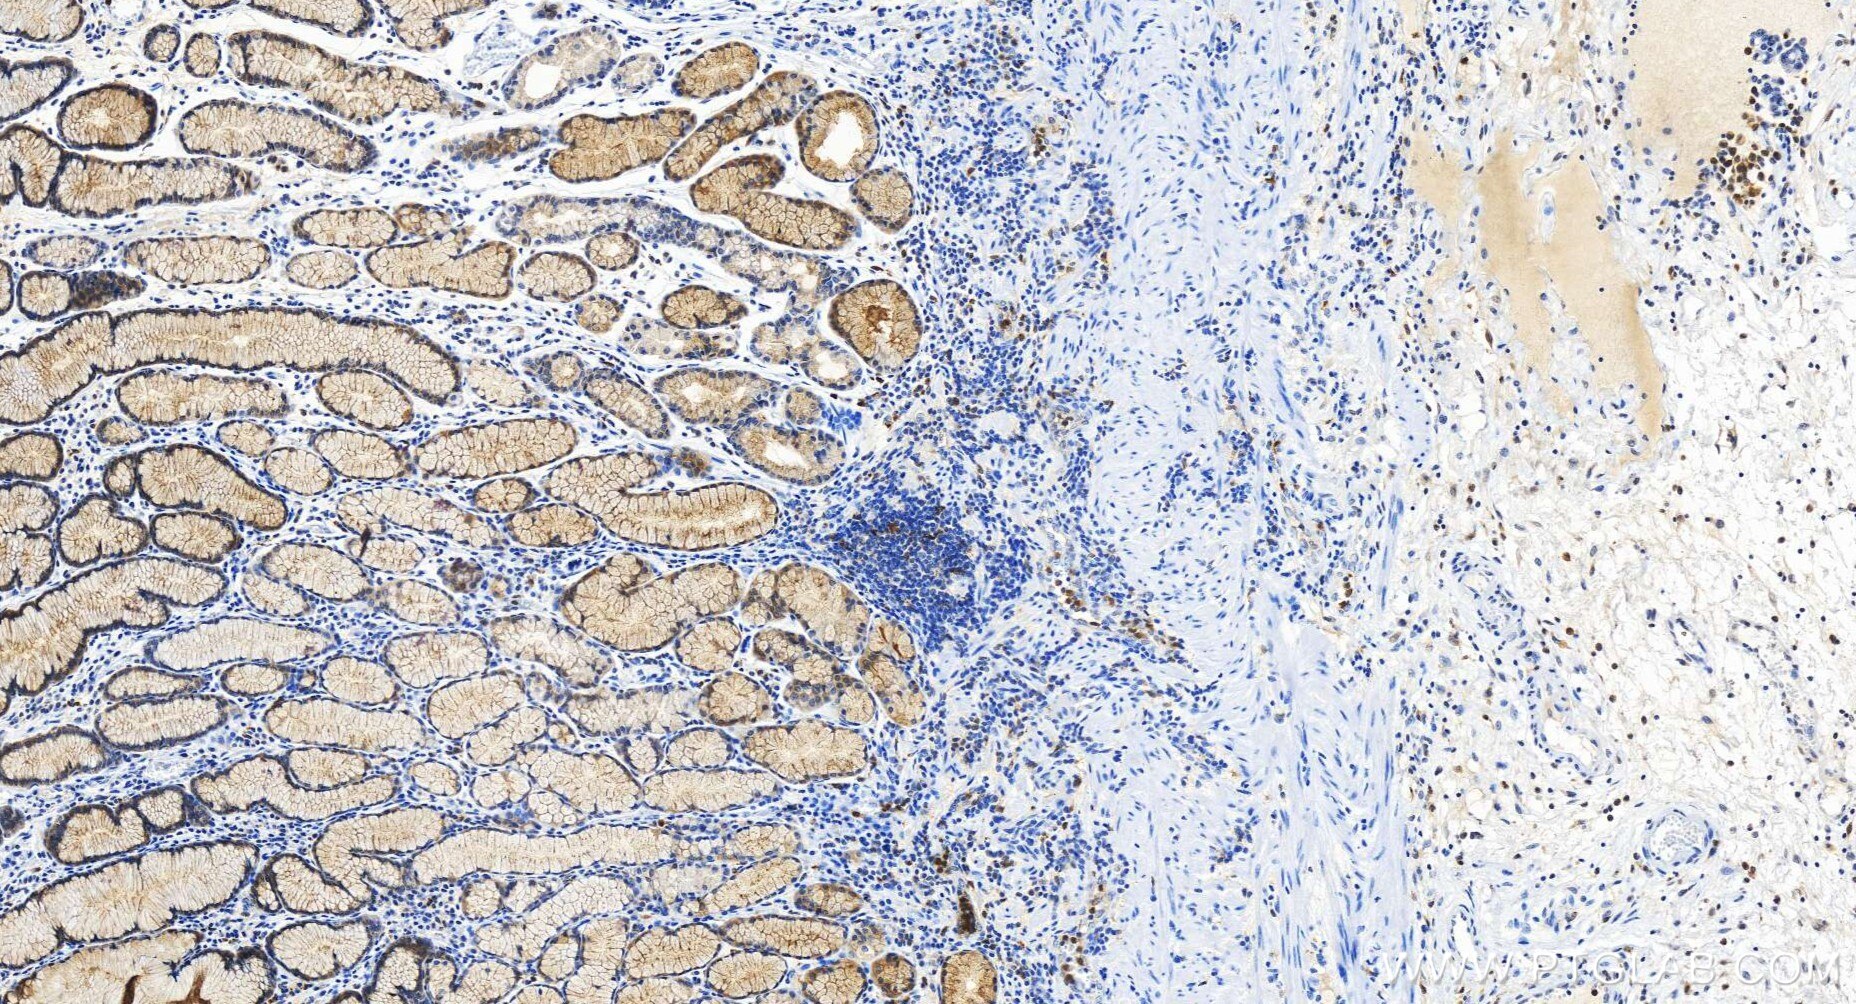

| Positive IHC detected in | human stomach cancer tissue Note: suggested antigen retrieval with TE buffer pH 9.0; (*) Alternatively, antigen retrieval may be performed with citrate buffer pH 6.0 |

| Immunohistochemistry (IHC) | IHC : 1:250-1:1000 |